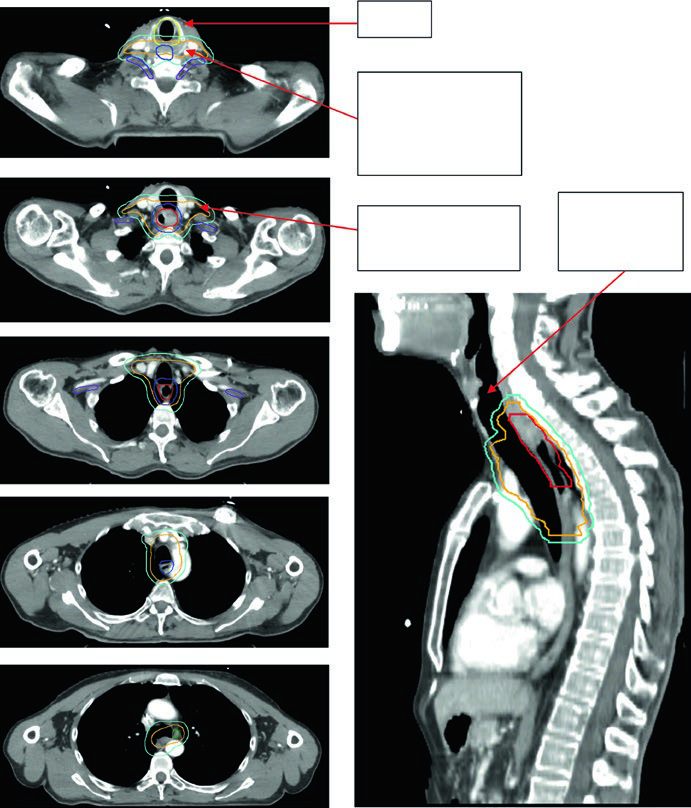

Caso 1: CEC Cervical/Torácico Superior — 69 anos

Paciente de 69 anos com CEC do esôfago cervical/torácico superior. O PET-CT revelou captação de FDG no tumor primário e linfonodos paratraqueais discretamente captantes. A EGD demonstrou massa ulcerada submucosa entre 15 e 23 cm dos incisivos. Os volumes delineados incluíram: plexo braquial (roxo), laringe (amarelo), GTV esofágico (vermelho), GTV nodal (verde), CTV (laranja), PTV 54 Gy (ciano) e PTV 60 Gy (azul escuro). O borda superior do campo supraclavicular foi posicionada na borda inferior da cartilagem cricoide, com cobertura nodal supraclavicular bilateral eletiva.